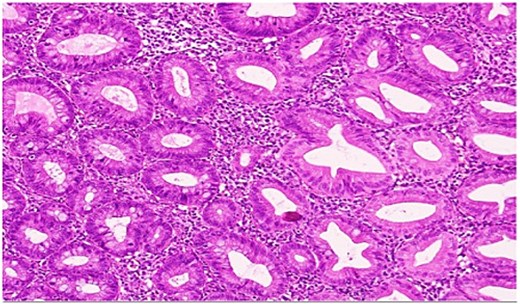

She underwent an uncomplicated laparoscopic appendectomy. Histopathology confirmed acute appendicitis and incidentally identified a serrated polyp confined to the mucosa without dysplasia or malignancy (Figs. 2—4). Postoperative recovery was uneventful; she was discharged stable and asymptomatic at 2-week follow-up. Given the incidental finding, colonoscopic evaluation was arranged to assess for synchronous colorectal lesions.

High-power view showing comparison of the adjacent normal appendiceal mucosa with unremarkable straight crypts lining the lumen and the serrated architecture of the polyp.